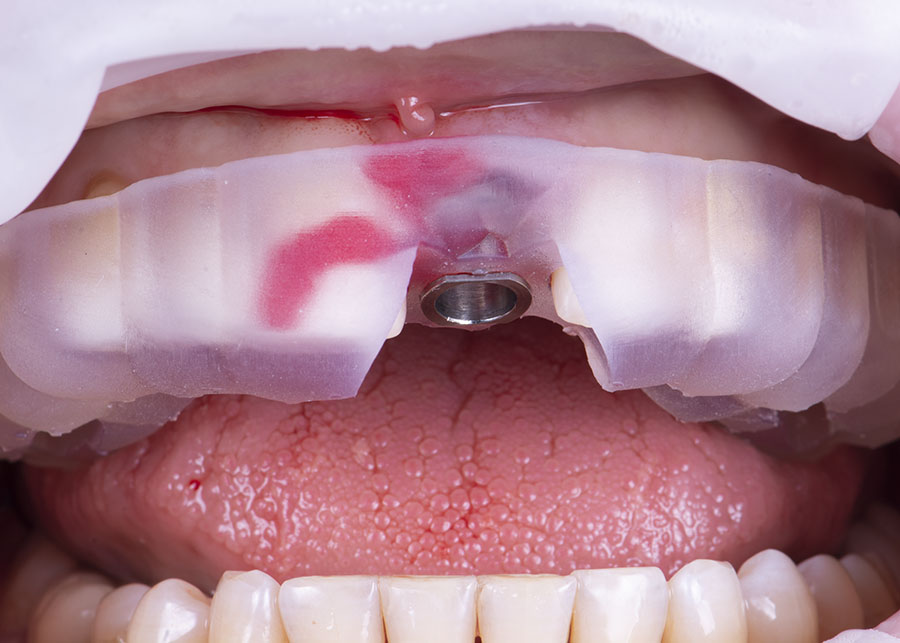

Диагностика

Диагностика включает в себя проведение различных исследований и обследований, которые помогают врачу получить полную и точную информацию о состоянии зубов, десен и окружающих тканей.

В настоящее время доступны следующие возможности для диагностики:

- Цифровая фотография.